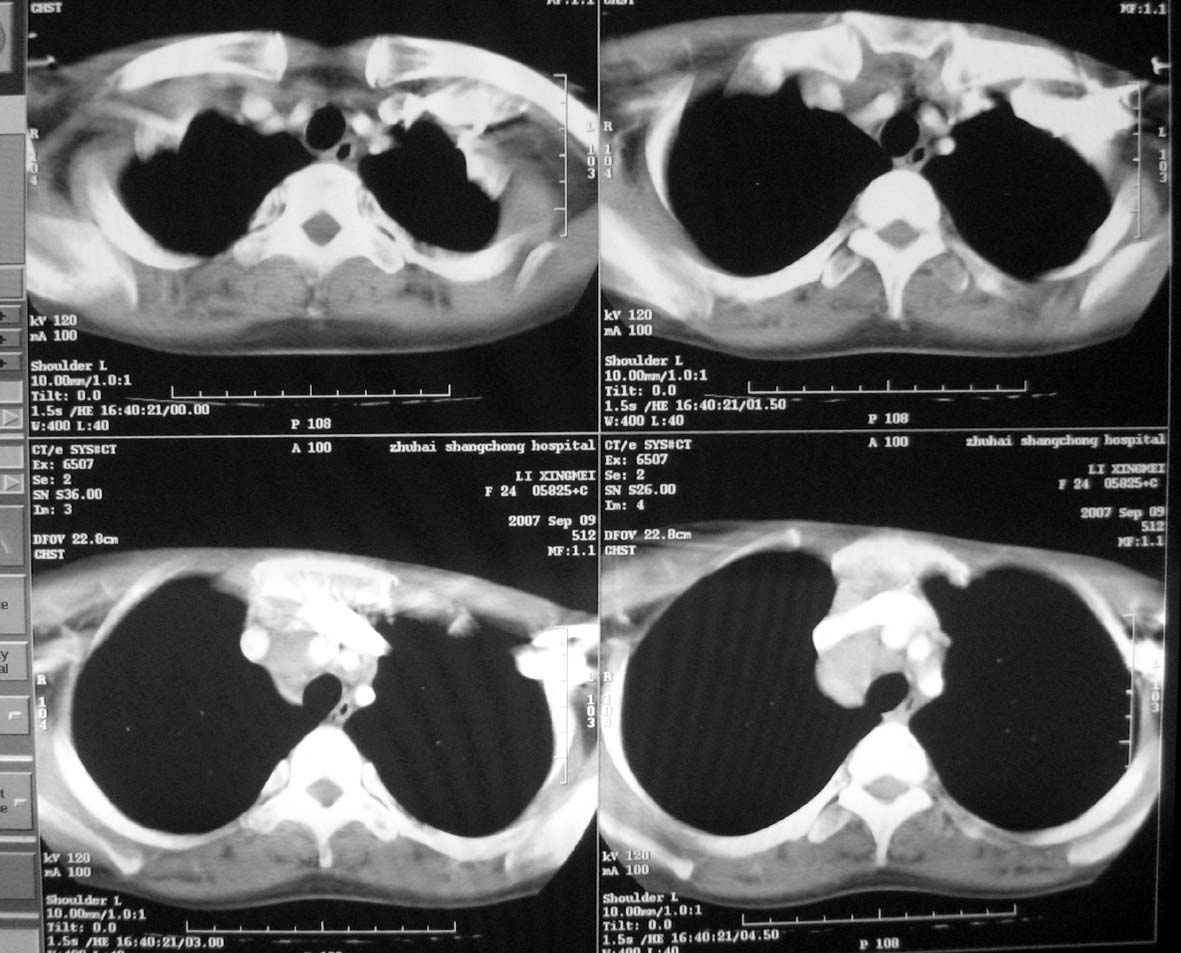

以下是引用qiuleiyu在2007-9-14 19:12:00的发言:[br]纵隔(气管旁组\\隆突下\\主动脉旁组\\血管前组)及肺门淋巴肿大,边界欠清.密度均匀,内无明确钙化.[br]结合临床症状考虑;结节病可能大.[br]鉴别;1,淋巴瘤,可有全身浅表淋巴肿大,肝脾大,发热等.肿大淋巴主要为气管旁组及血管前组及主动脉旁组,肺门肿大不明显.典型者为冰冻纵隔.[br] 2,转移瘤;多见于肺癌,按淋巴链分布肿大,单侧肿大多见,常可见坏死.[br] 3,castlemans;增强后明显血管样强化.内部可有分支状钙化,蜘蛛状瘢痕.周边可有粗大血管.[br] 4,结核;67%有肺部结核灶,肿大淋巴结节,内部可有钙化,增强环状或分格样强化.